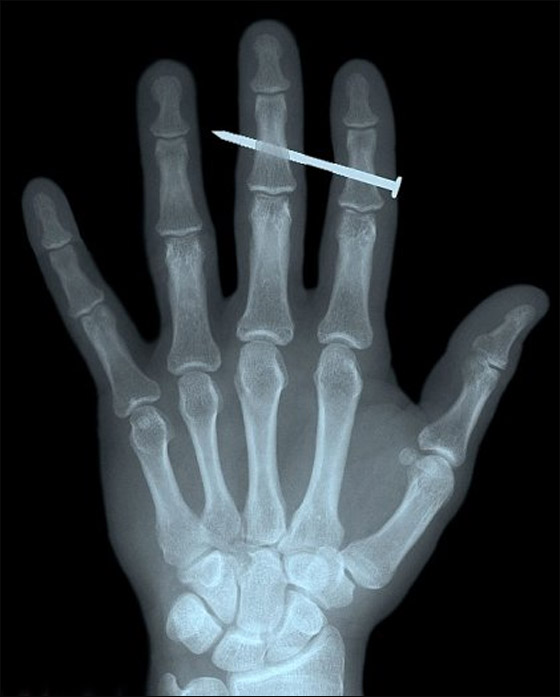

غير أن صورا أخرى مثل صورة الإصبع المقطوع أو المسمار الذي يخترق إصبعا مرعبة أكثر مما هي طريفة.

مسمار يخترق عظم اصبع